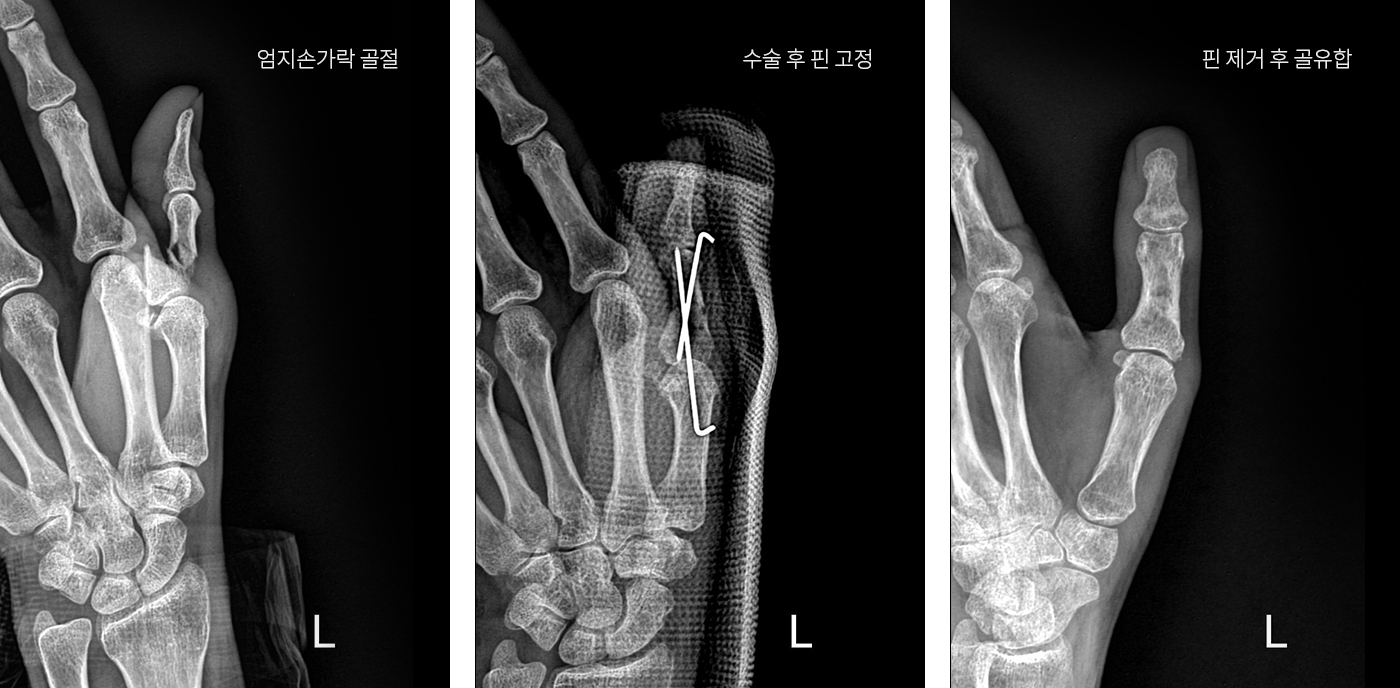

골절은 비수술적 치료와 수술적 치료로 나눌 수 있습니다. 비수술적 치료는 골절이 되어 어긋나 있는 뼈를 바로 맞추는 도수정복 시술이나 석고 붕대를 이용한 기브스를 통해 고정해 주는 방법이 있습니다. 수술적 치료는 골절부 상하에 핀을 삽입한 후 외부에서 석고 붕대 고정이나 금속 기기를 이용해 골절을 고정해 주는 외고정 방법과 골절 부위를 정복하고 내고정 기구를 이용해 골절을 고정해 주는 내고정 방법이 있습니다.